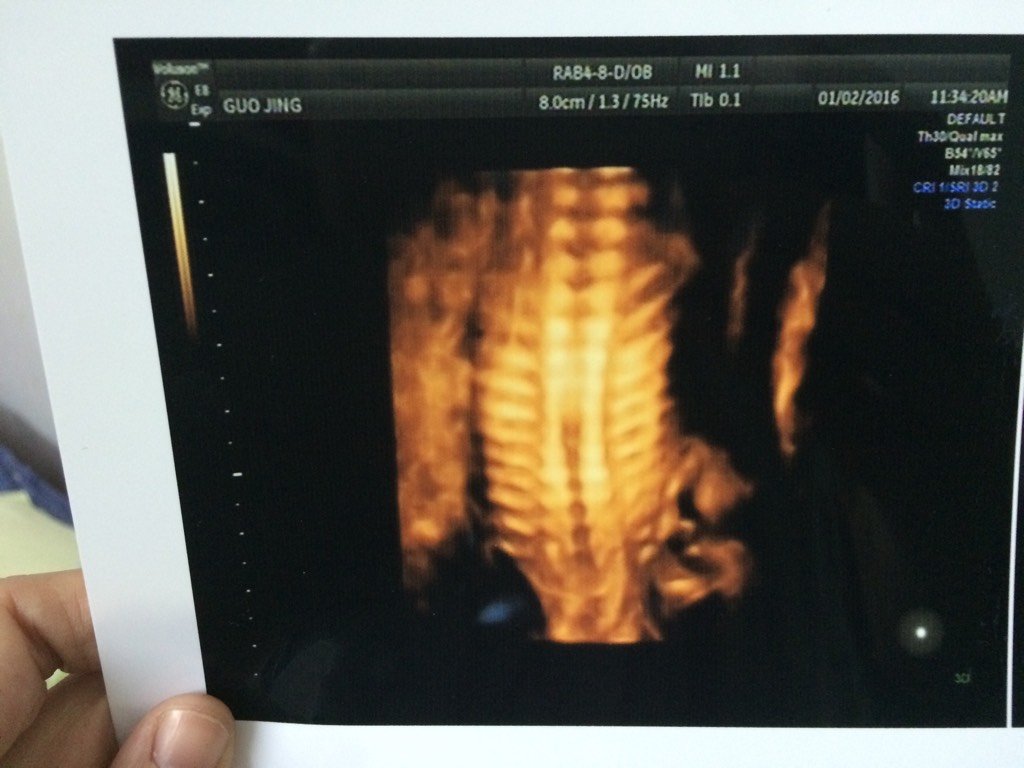

胎儿胸段脊柱排列欠规则严重吗?现在22周了,医生要过一个月再去复查 胎儿胸段脊柱排列欠规则严重吗?现在22周了,医生要过一个月再去复查, 点击展开 女巫_wqAH 2016-01-11 15:12 为您推荐: 其他回答 那就听医生的 微笑糖 2016-01-11 16:05 听医生的去看 魏啥 2016-01-11 16:00 听医生吧, 茹茹的娘亲 2016-01-11 15:56 听医生的,,, 怀孕妈咪 2016-01-11 15:47 听医生的就行 幽笑 2016-01-11 15:45 加载更多 相关问题 怀孕37周加5天,彩超显示脊柱排列尚规则,完整是啥意思 宫腔内见一胎儿回声,脊柱排列规则,胎心搏动和胎动可见,胃泡可见双顶径23mm 股骨长9mm 羊水 34周B超胎儿头位,双顶径8 8cm,头围29cm,侧脑室0 6cm,股骨6 5cm,腹径9 3cm,腹围27cm 脑中线居中 脊柱连续,排列规则,可见胎心搏动,排列规则,胎盘前壁,厚约3 1cm,呈I级 羊水透声好,羊水指